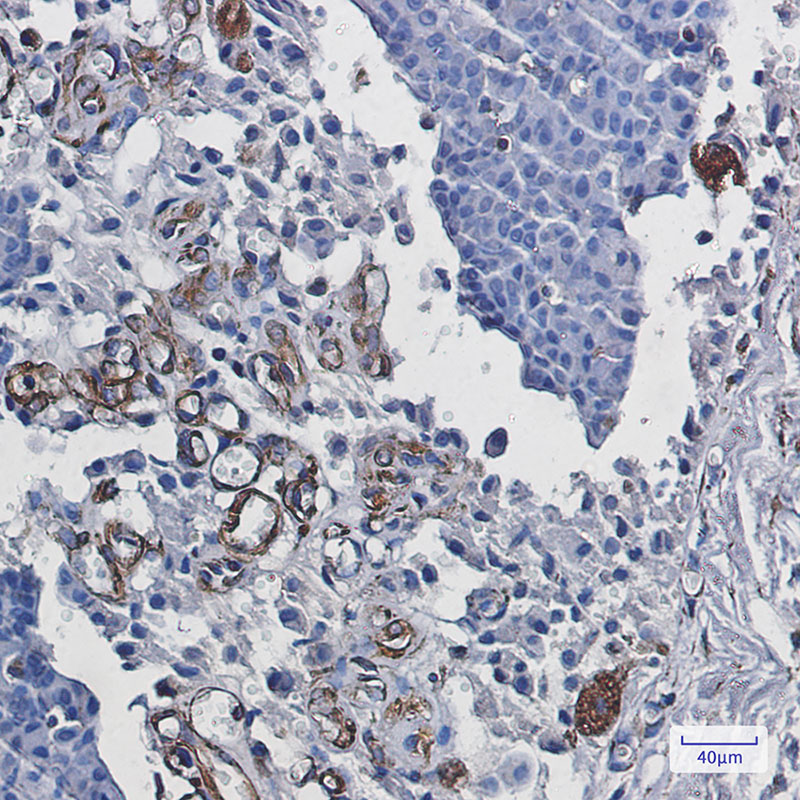

推荐稀释比 WB:1/500-1/1000;IHC:1/50-1/100

Immunohistochemistry analysis of paraffin-embedded Human breast cancer using Staufen antibody.High-pressure and temperature Sodium Citrate pH 6.0 was used for antigen retrieval.